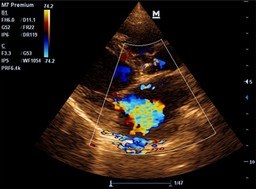

Kardiologia

W trosce o serca naszych pupili wykonujemy w naszej Przychodni badania EKG i ECHO serca.

Badania te wykonywane są przez personel biorący regularny udział w szkoleniach z zakresu kardiologii weterynaryjnej.

To wszystko pozwalają nam na wczesne wykrycie i zdiagnozowanie ewentualnej choroby serca oraz podjęcie odpowiedniej terapii.

Po diagnostyce w razie potrzeby wdrażamy leczenie farmakologiczne oraz zapewniamy stały monitoring i prowadzenie naszych pacjentów.